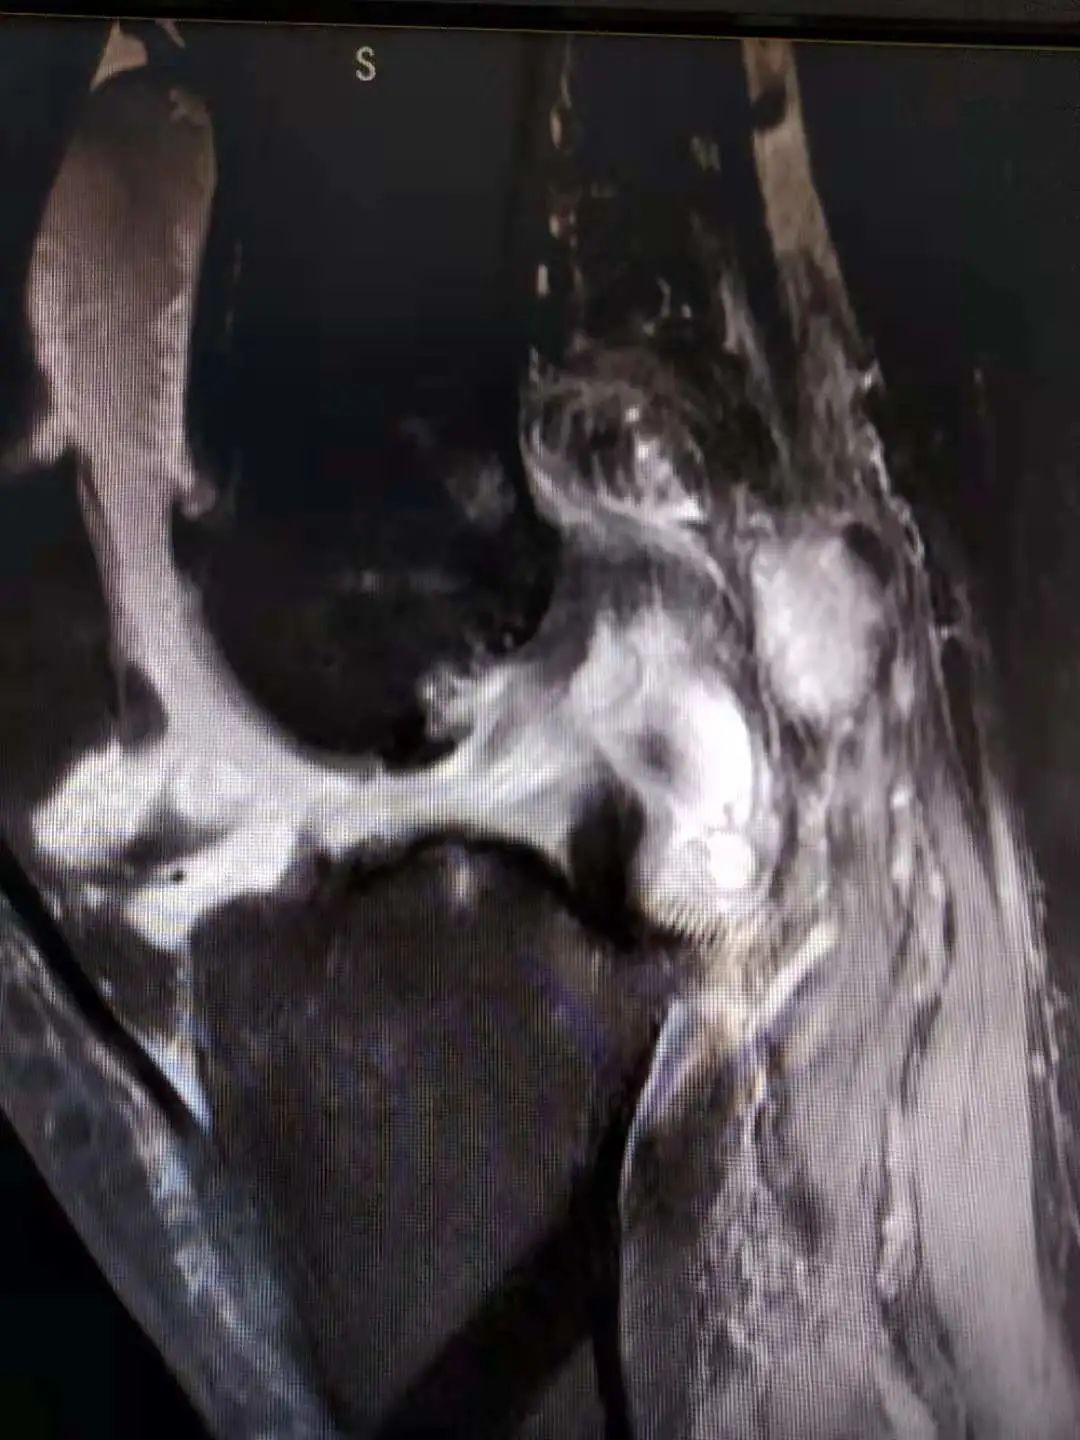

术前半月板损伤表现及前交叉韧带损伤表现

日前,张女士因车祸导致右膝部损伤,来到我院骨科二区病房住院治疗。突如其来的外伤让张女士惊魂未定,副主任冯翠军一边安慰她一边为其检查,发现她右膝部肿胀、压痛、旋转挤压试验阳性,为其急查右膝部MRI发现右膝部大量积液、前交叉韧带损伤、内外侧半月板损伤。依据患者的情况,曾在毓璜顶医院进修关节科的主治医师刘月皓提出行膝关节镜手术检查及治疗更有利于患者,这一提议经科室讨论后得到大家的一致认可。